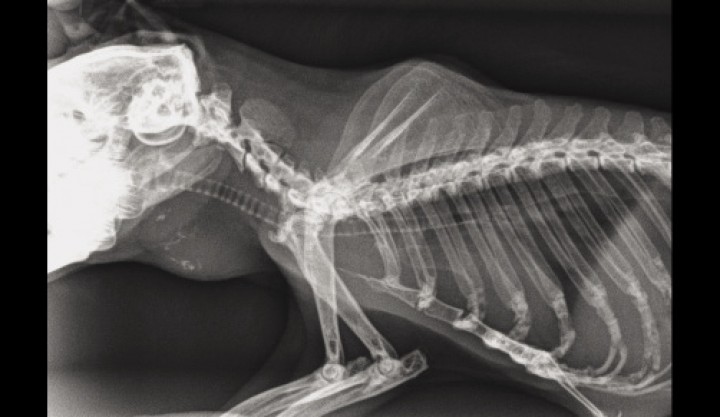

La radiografía torácica mostraba una evolución en su enfermedad cardíaca, con aumento del tamaño de la silueta cardiaca y mineralización de la aorta y de las zonas centrales del nódulo tiroideo (Fig. 3). La mineralización de los nódulos es un hallazgo frecuente, aunque no es un indicativo de malignidad.[ Brandao J, Vergneau-Grosset C, Mayer J. Hypertiroidism and Hyperparathyroidism in Guinea pigs (Cavia porcellus). Vet Clin Exot Anim 2013; 16:407-42. ]

<p>Radiografía lateral del tórax. Se observa calcificación del nódulo y mineralización de la aorta.</p>

Figura 3

Radiografía lateral del tórax. Se observa calcificación del nódulo y mineralización de la aorta.